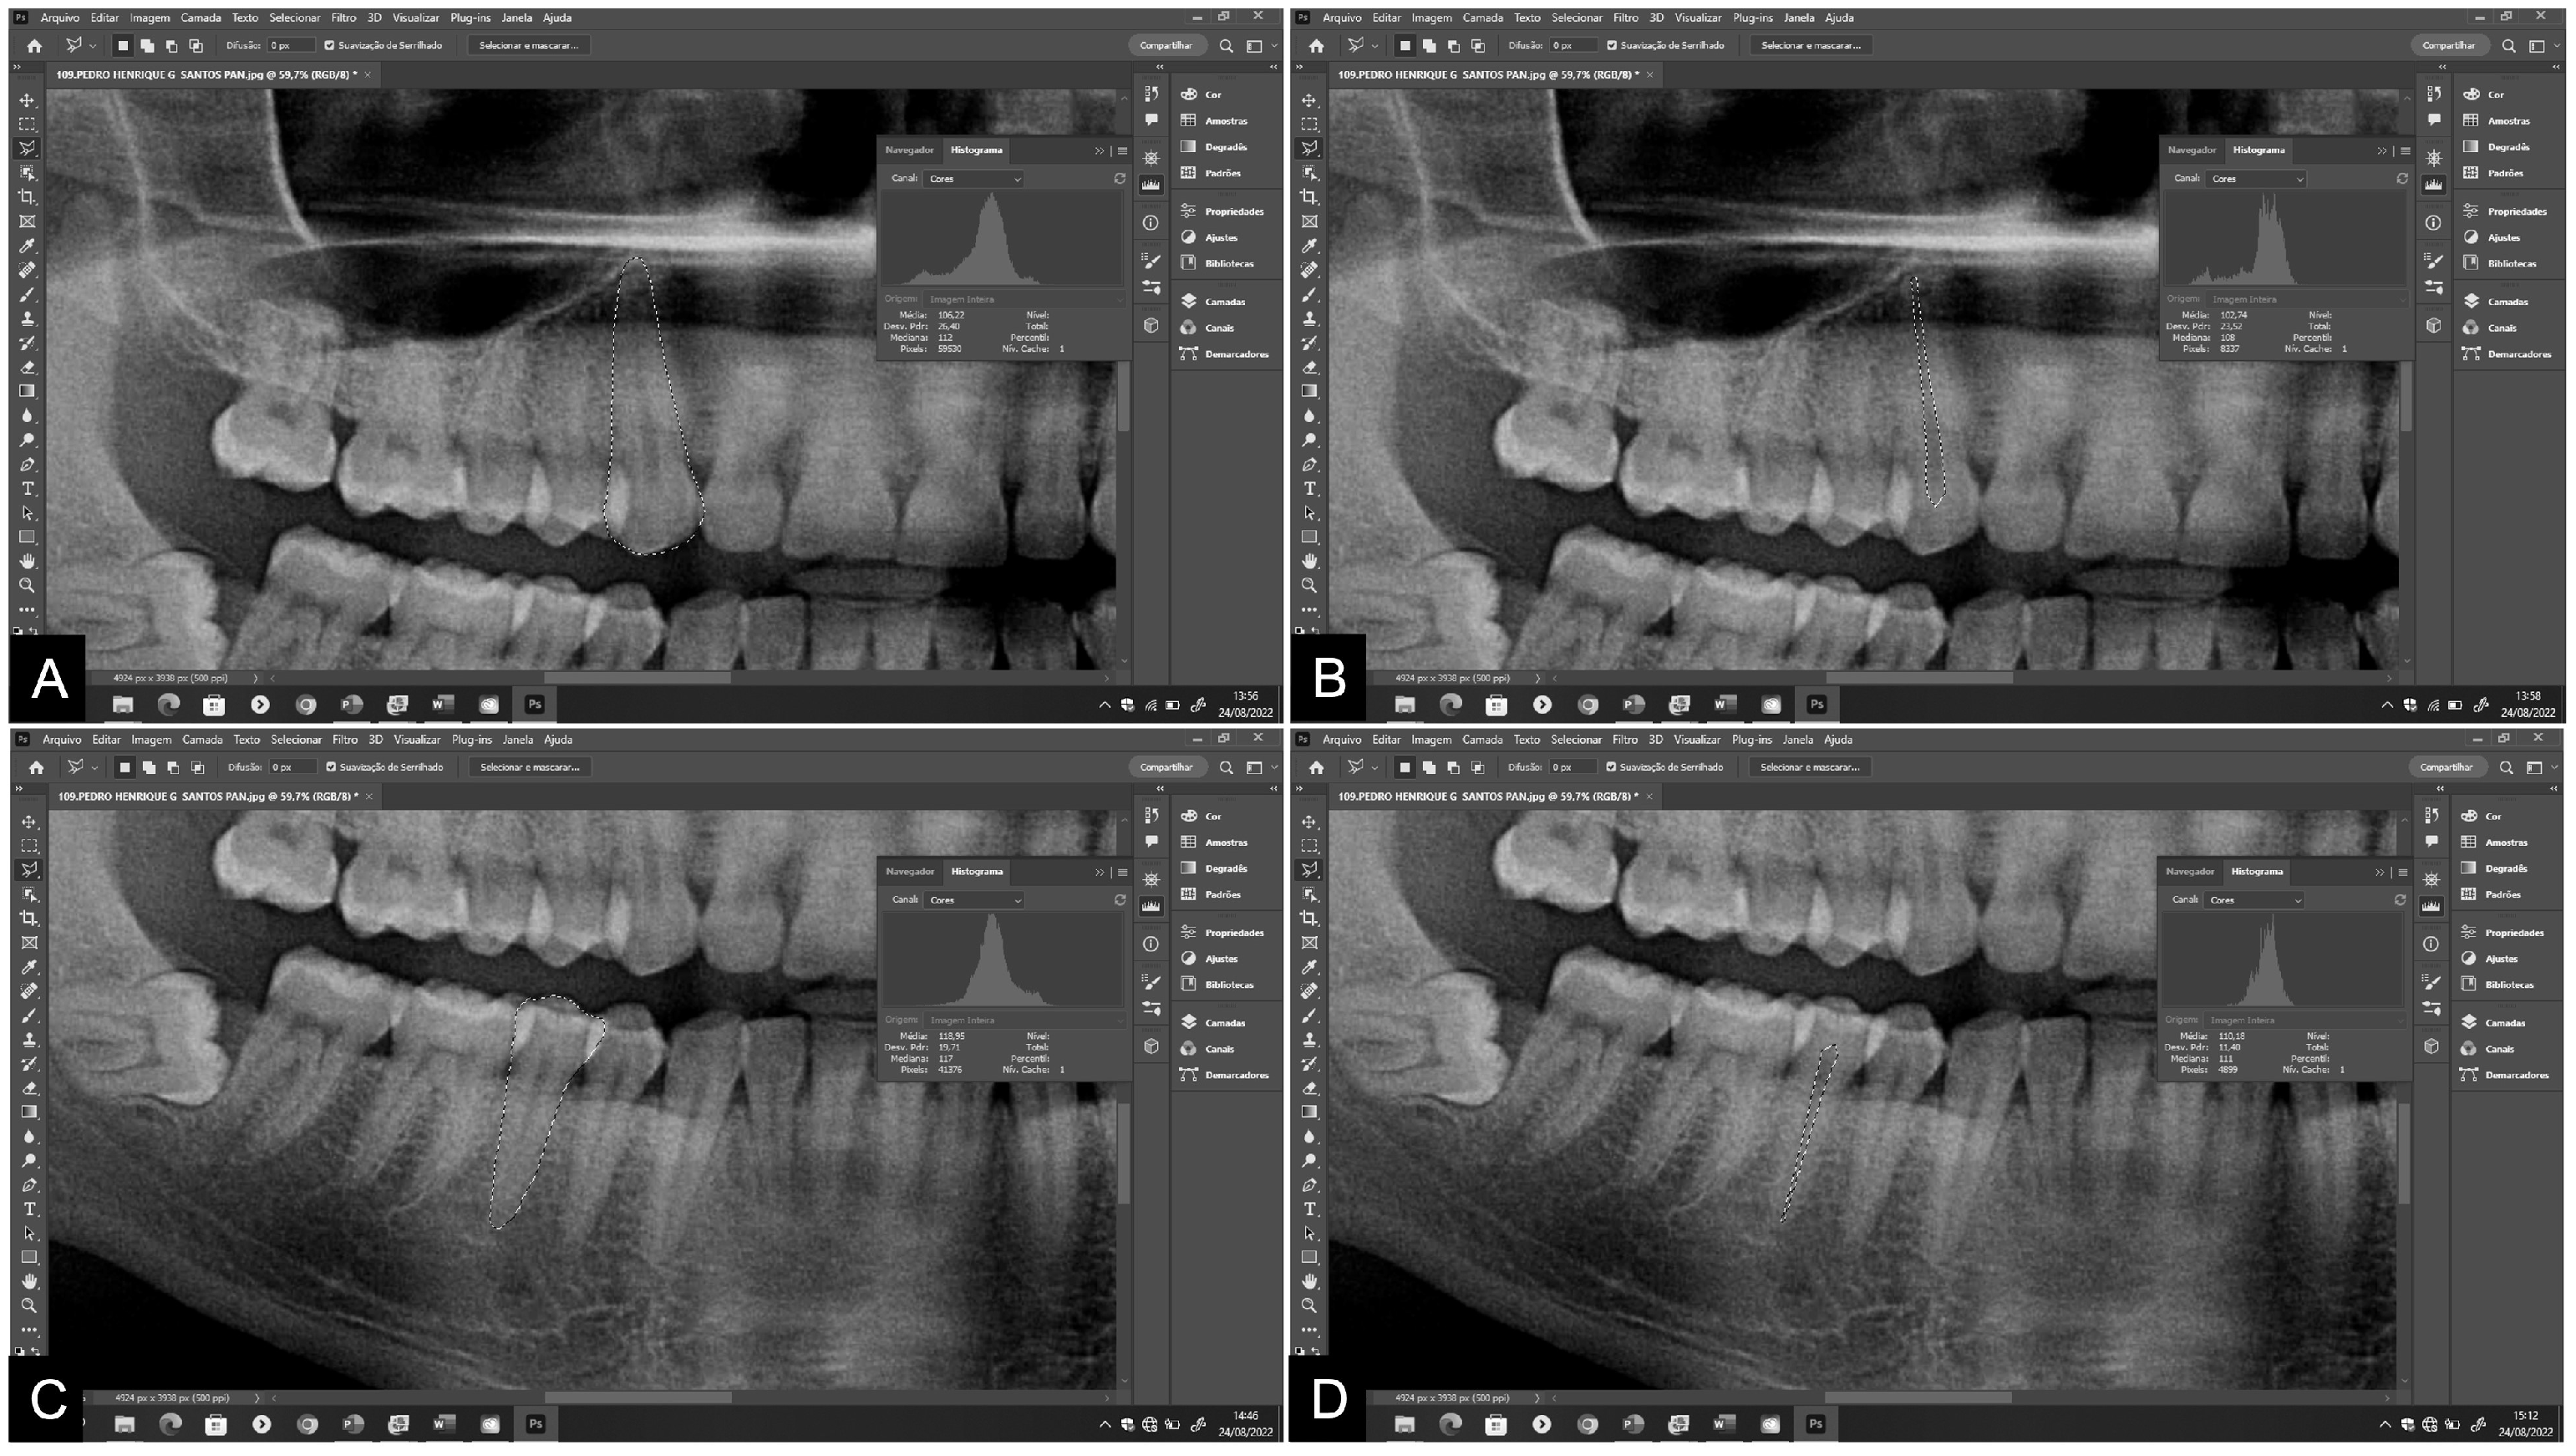

The points were marked, and the dental structures delineated using the polygonal lasso tool of the Adobe Photoshop CS4® program (Adobe Systems Inc., San Jose, CA, USA). A high-resolution Samsung® monitor, model S24E310 (Samsung, Manaus, AM, Brazil), was used for image visualization. All images were outlined using a pen and Huon® Inspiroy 420 graphics tablet (Shenzhen Huion Animation Technology Co. Ltd., Shenzhen, Guangdong, China). The teeth were classified according to the FDI World Dental Federation notation [32]. Initially, teeth 13 and 45 were evaluated. In the absence of either of these, teeth 23 and 35 were evaluated. Measurements were taken on the maxillary canine and mandibular second premolar on panoramic radiographs, followed by measurements on periapical radiographs. At least 20 points outlining the contour of the tooth and at least 10 points delineating the contour of the pulp were marked (Figure 1 and Figure 2). This process determined the total area in pixels of the tooth and pulp [2,5,11-13].

Figure 1. Measurements of tooth and pulp areas and pixel values on panoramic radiograph. (a-b) maxillary canine; (c-d) mandibular second premolar.